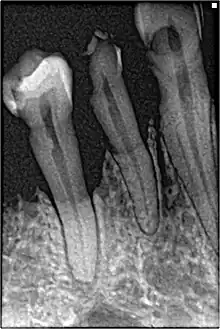

Abscessed tooth periapical radiograph

The 2018 Disease Classification of Periodontal Disease and Conditions contains a category for other conditions that may have an effect upon the health of the periodontium.[7]